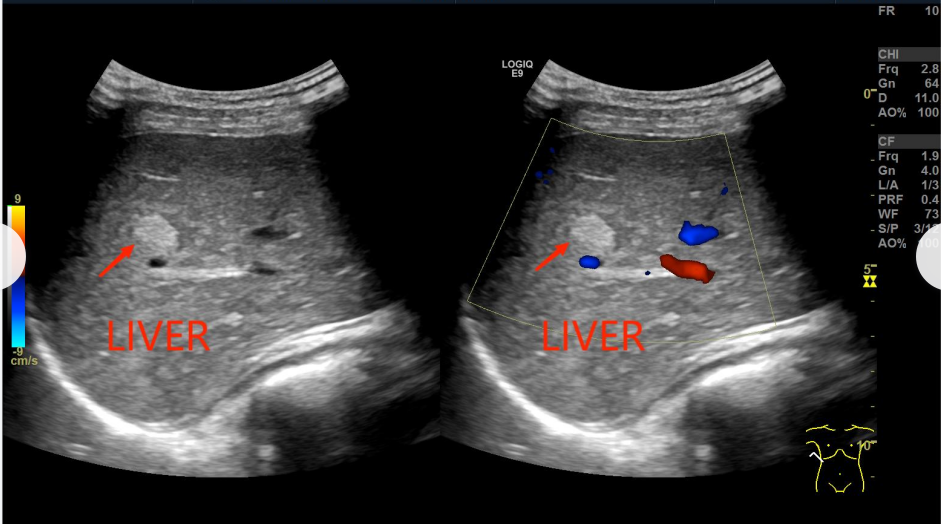

巨大血管瘤对右肾有压迫